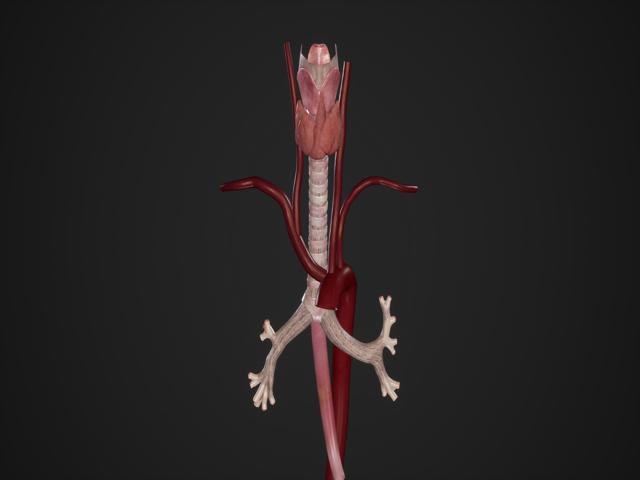

Yırtığın kalpten çıkan ana damarda başladığını ve aşağı inerek kalbi besleyen damarları tıkayabileceğini belirten Prof. Dr. Köksal, şu bilgileri verdi:

“Sırrı Süreyya Önder’in kalp krizi geçirmesinin nedeni sağ koroner damarının bu yırtık nedeniyle tıkanmasıydı.Yırtık yukarıya çıktığında ise beyne giden kan azalabilir, bu da bayılma şikâyetleriyle kendini gösterebilir. Bu durum, hayati tehlikenin çok yüksek olduğunu gösterir.”

Aort çapı normalin üzerinde olan, kontrolsüz tansiyonu bulunan bireylerin düzenli takip altında olması gerektiğini söyleyen Prof. Dr. Köksal, “Bu hastaların yılda en az bir kez tomografi ile takip edilmesi gerekir.

Tansiyonun mutlaka düzenli kontrol altında tutulması şart. Çünkü aort damarındaki yırtılma, tıpkı koroner damarlarındaki gibi önceden sinyal vermez. Göğüste ani bir yırtılma hissi, saplanan ağrı, bayılma ve tansiyon düşüklüğü gibi belirtilerle kendini gösterir” şeklinde konuştu.